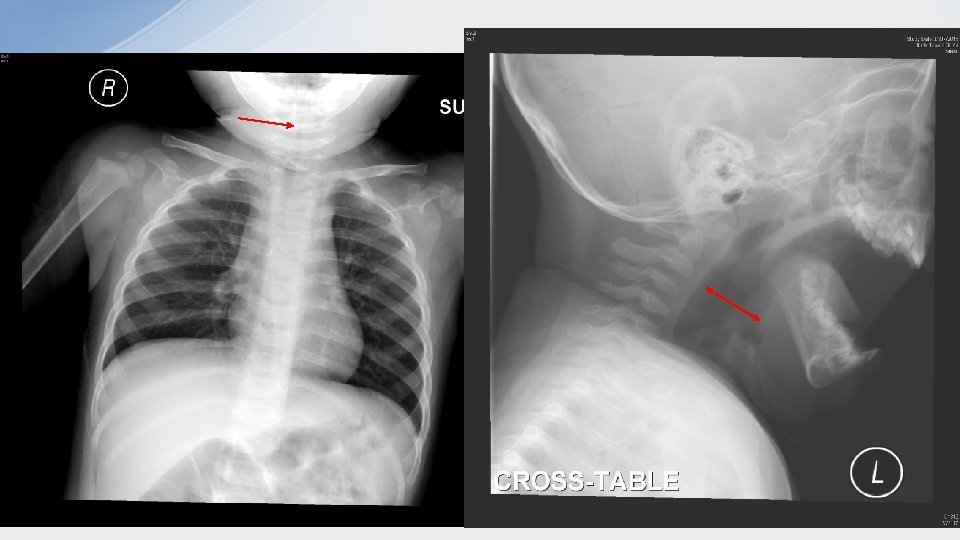

Case 2. • • • 11/F good past health no urine output and suprapubic distension for 12 hrs. bowel opening P/E: suprapubic mass + Bedside USG was preformed

• 1. What is the USG finding? – distended fluid-filled vagina (Hematocolpos) and uterus (hematometra) • 2. What history would you like to ask? – menstruation history

• 3. What is the diagnosis? – Imperforate hymen • 4. What is the treatment? – Insert foley catheter – Surgical repair